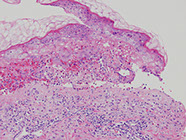

Erythema multiforme (EM)

Blistering skin disorder assoc w infx (M. pneumoniae, HSV), drugs (sulfas, B-lactams, phenytoin) cancer, autoimmune dz

Histology: Interface dermatidities - superficial lymphocytic infiltrates around vessels which migrate up to DEJ causing edema and eventually invade upper dermis levels

- vacuolar interface change, scattered necrotic keratinocytes, interface lymphocytes

Normal corneum (basket-weave orthokeratosis) with crazy necrosis underneath corneum which is out of proportion to the amount of inflam (primarily lymphs in early phases) and basal layer vacuolization

Erythema multiforme

Stevens-Johnson syndrome

EM